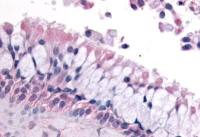

IHC-P analysis of human brain tissue (left) and rat brain tissue (right) using GTX60464 GluR3 antibody [1D2].